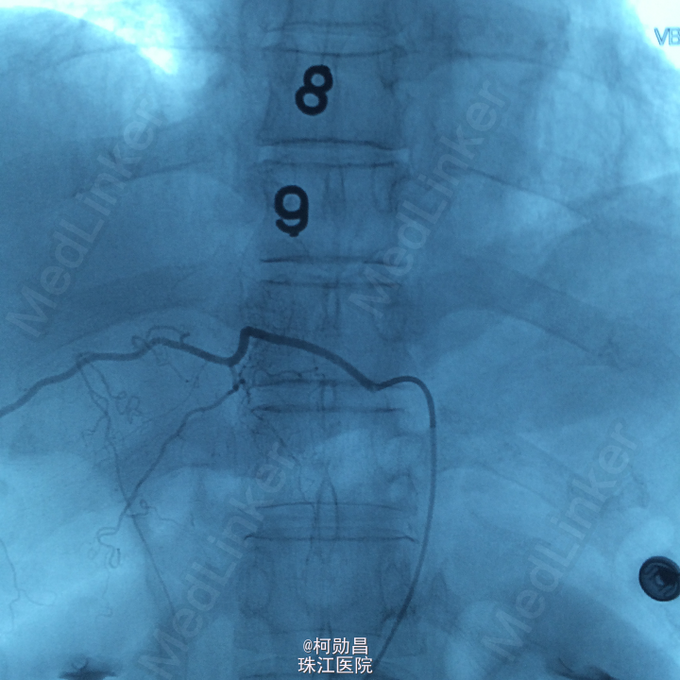

诊断:硬脊膜动静脉瘘 处理:予全麻下行栓塞治疗,选择予 withn-butyle-2-cyanoacrylate(医用胶)完全闭塞 。